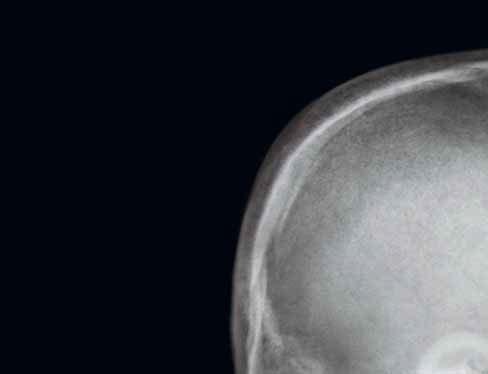

1 lamina externa

2 diploe

3 lamina interna

4 sutura coronalis (šev korunový)

5 sulcus arteriae meningeae mediae